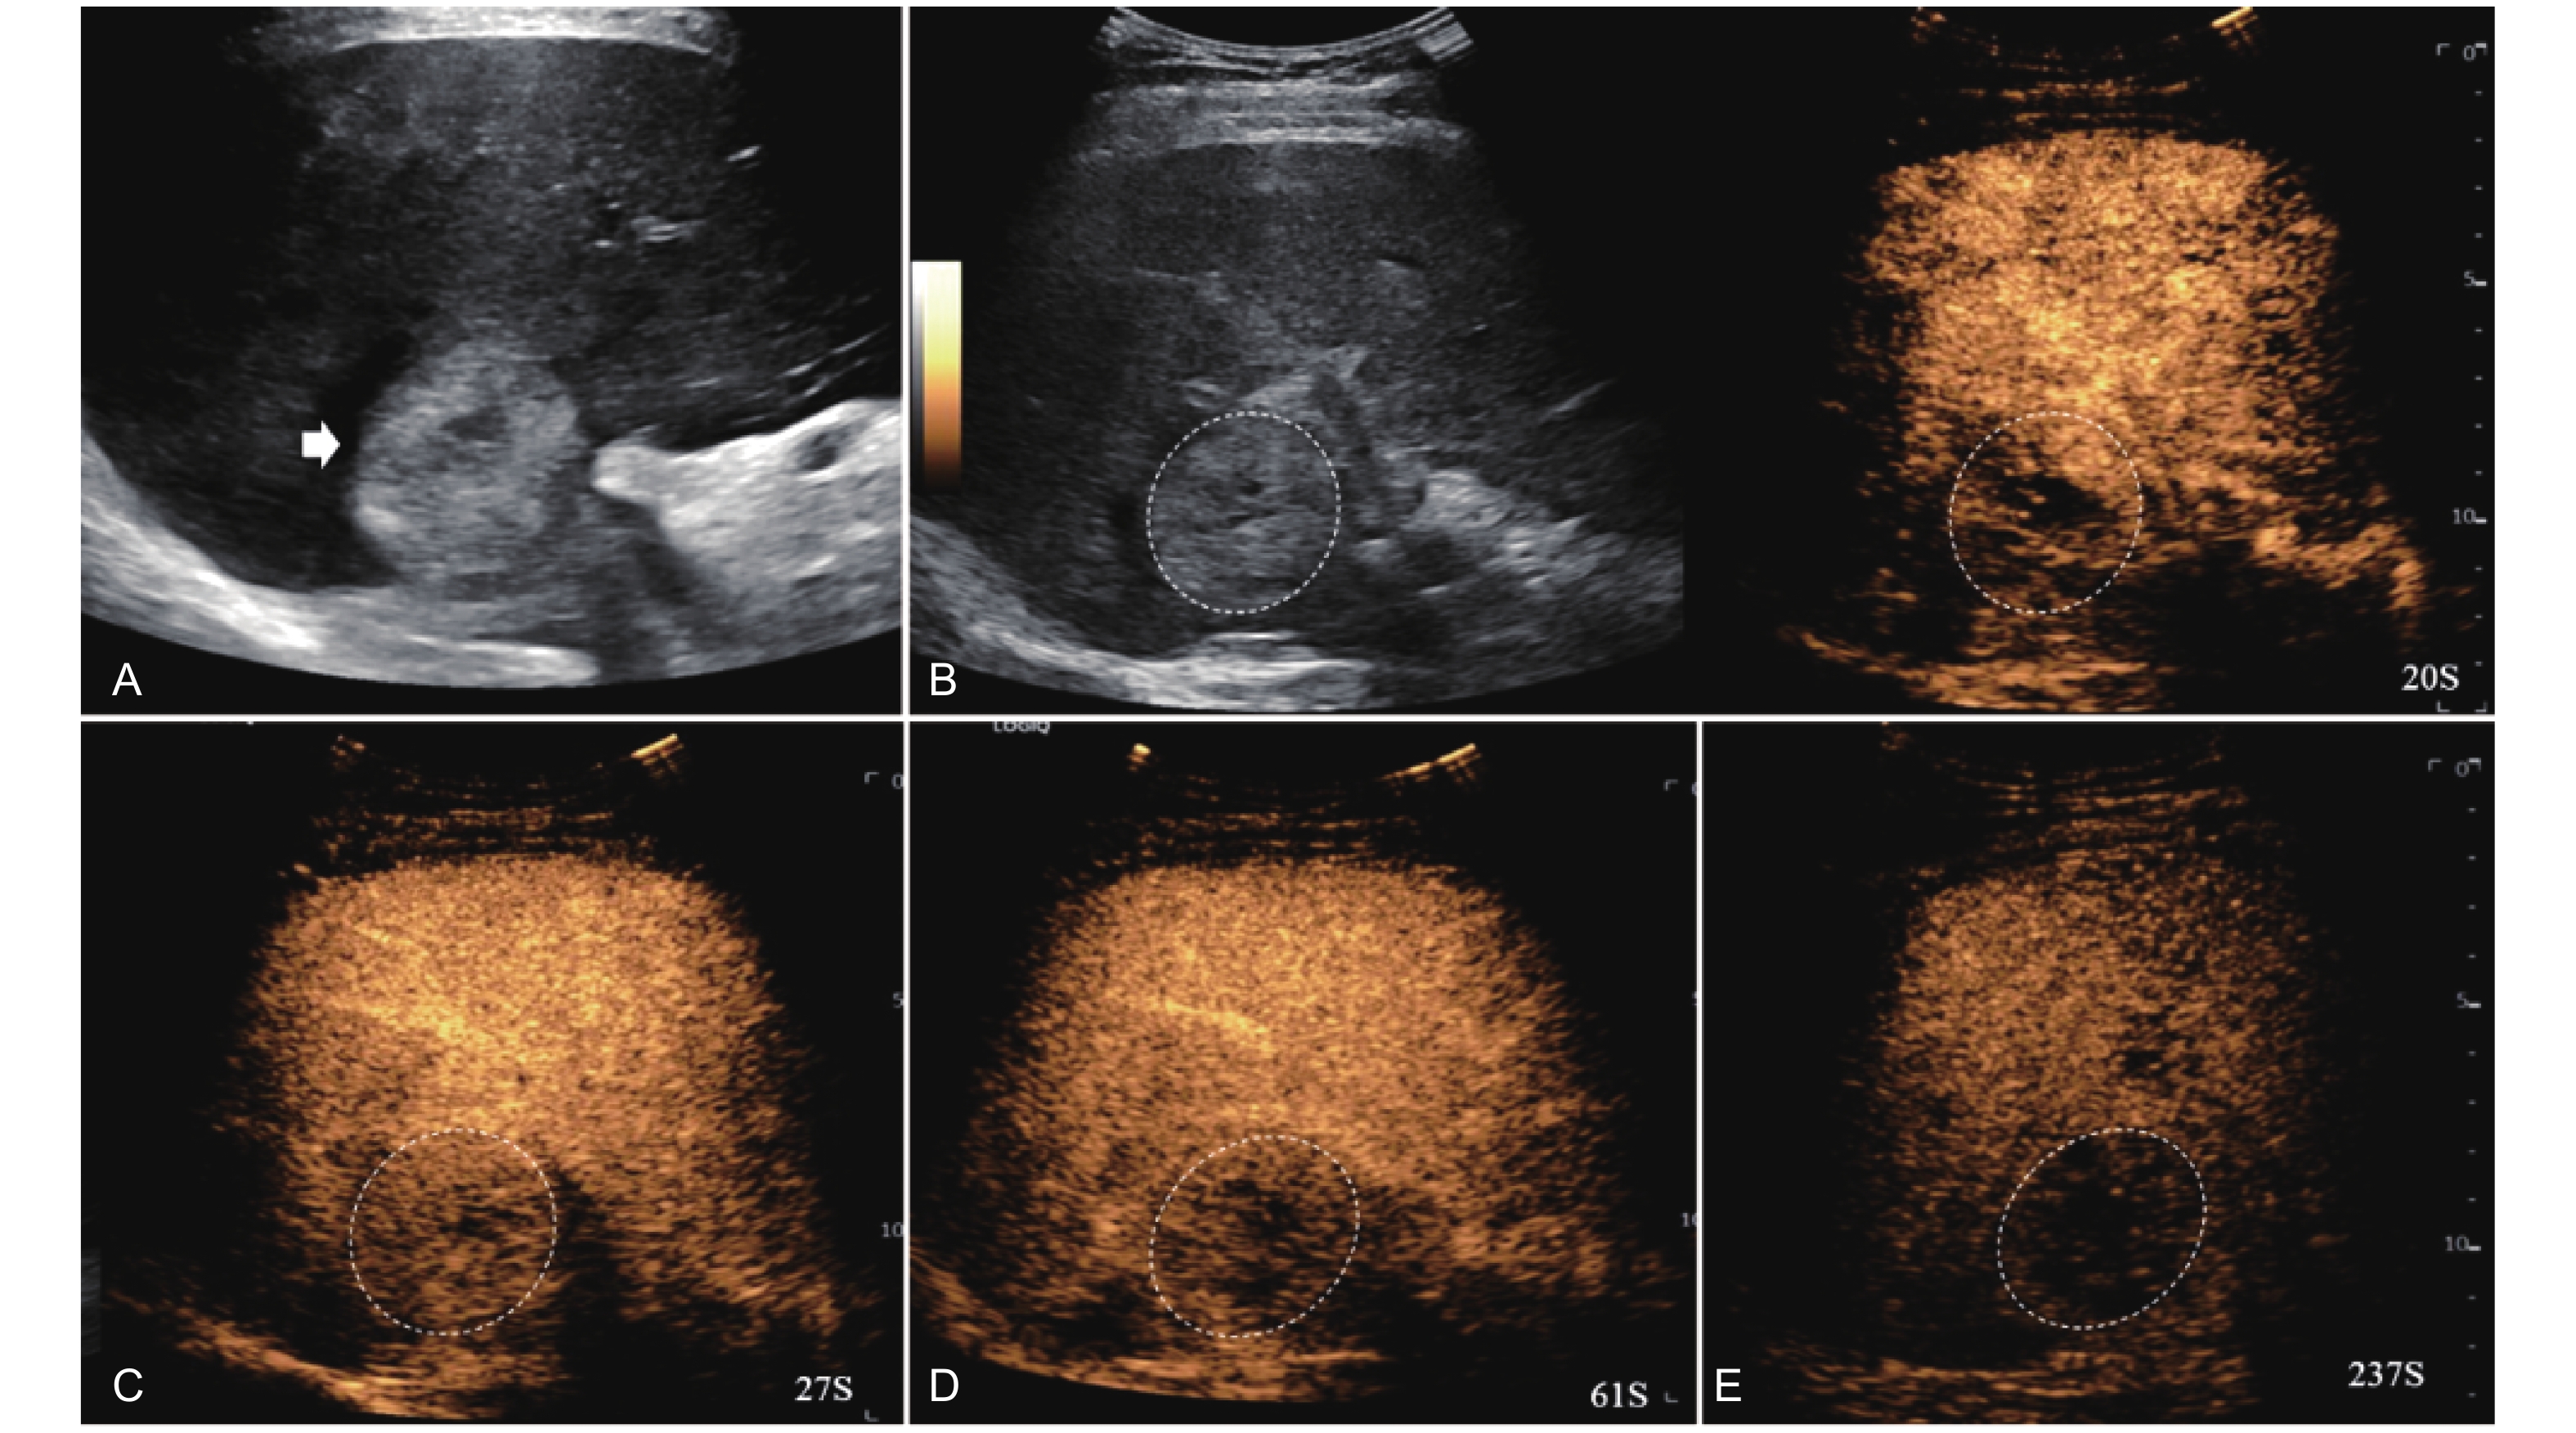

Figure 15

LR-TR Viable. Example of a treated tumor 29 days after TACE. (A) B-mode image shows a heterogeneous mildly hypoechogenic lesion with well-defined margins (thick arrow), measuring 85 mm in segment II and III; (B-C) CEUS shows partial intralesional hyperenhancement with perilesional hyperenhancement (thin arrow) during the arterial phase; (D-E) The lesion shows intralesional and perilesional (thin arrow) gradual washout in the portal venous and late phases. Findings are consistent with LR-TR Viable."